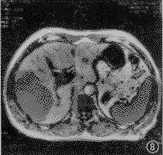

图7,8 患者 男,34岁。肝右叶肝癌而不伴有脂肪浸润。肝癌病灶在同相位(图7)和反相位(图8)序列上均显示非常清楚。肝与脾和病灶信噪比和对比信噪比在2种序列上均无显著差异(P>0.05)